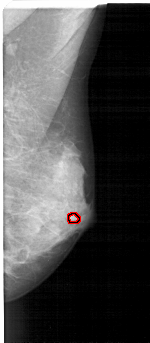

A_1606_1.LEFT_MLO

RIGHT_MLO LINES 5131 PIXELS_PER_LINE 2236 BITS_PER_PIXEL 12 RESOLUTION 43.5 OVERLAY

FILE: A_1606_1.RIGHT_MLO.OVERLAY

TOTAL_ABNORMALITIES 1

ABNORMALITY 1

LESION_TYPE MASS SHAPE LOBULATED MARGINS OBSCURED

ASSESSMENT 4

SUBTLETY 2

PATHOLOGY BENIGN

TOTAL_OUTLINES 1

BOUNDARY